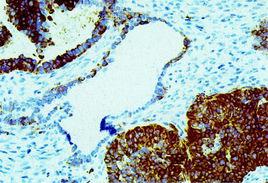

人睪丸支持細胞中INH-α樣免疫反應3.卵巢性索間質腫瘤與其他卵巢腫瘤:依靠病理學檢查有時難以鑑別卵巢性索間質腫瘤與其他腫瘤如纖維肉瘤、子宮內膜間質肉瘤、部分轉移癌等,而抗抑制素染色可以發揮輔助診斷作用。專家研究發現,性索間質腫瘤抗抑制素染色陽性。套用該方法,卵巢顆粒細胞瘤、泡膜細胞瘤、睪丸間質細胞瘤等性索間質腫瘤染色陽性,而其他腫瘤如子宮內膜間質肉瘤、胃腸道轉移肉瘤、小細胞癌等染色陰性。而且進一步指出抗抑制素抗體,特別是抗α亞單位抗體在性索間質腫瘤中表現陽性,可以用於排除與性索間質腫瘤類似的其他卵巢病變。但報導的病例較少,尚需積累資料。